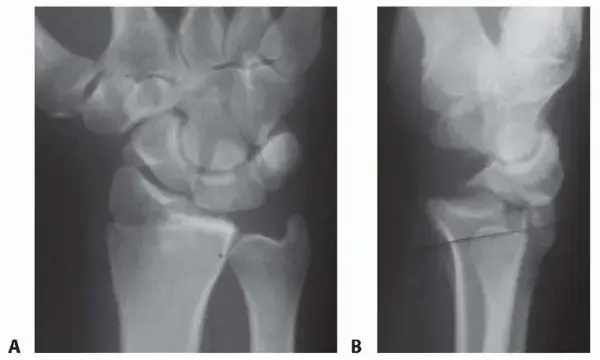

1. الأشعة السينية (X-rays):

• هي الخطوة الأولى والأساسية لتشخيص كسر الرسغ.

• توفر صورًا للعظام من زوايا مختلفة (عادةً ثلاث زوايا على الأقل) لتحديد وجود الكسر، موقعه، ومدى انزياحه.

• تساعد في تقييم ما إذا كان الكسر بسيطًا، مفتتًا، أو يؤثر على السطح المفصلي.